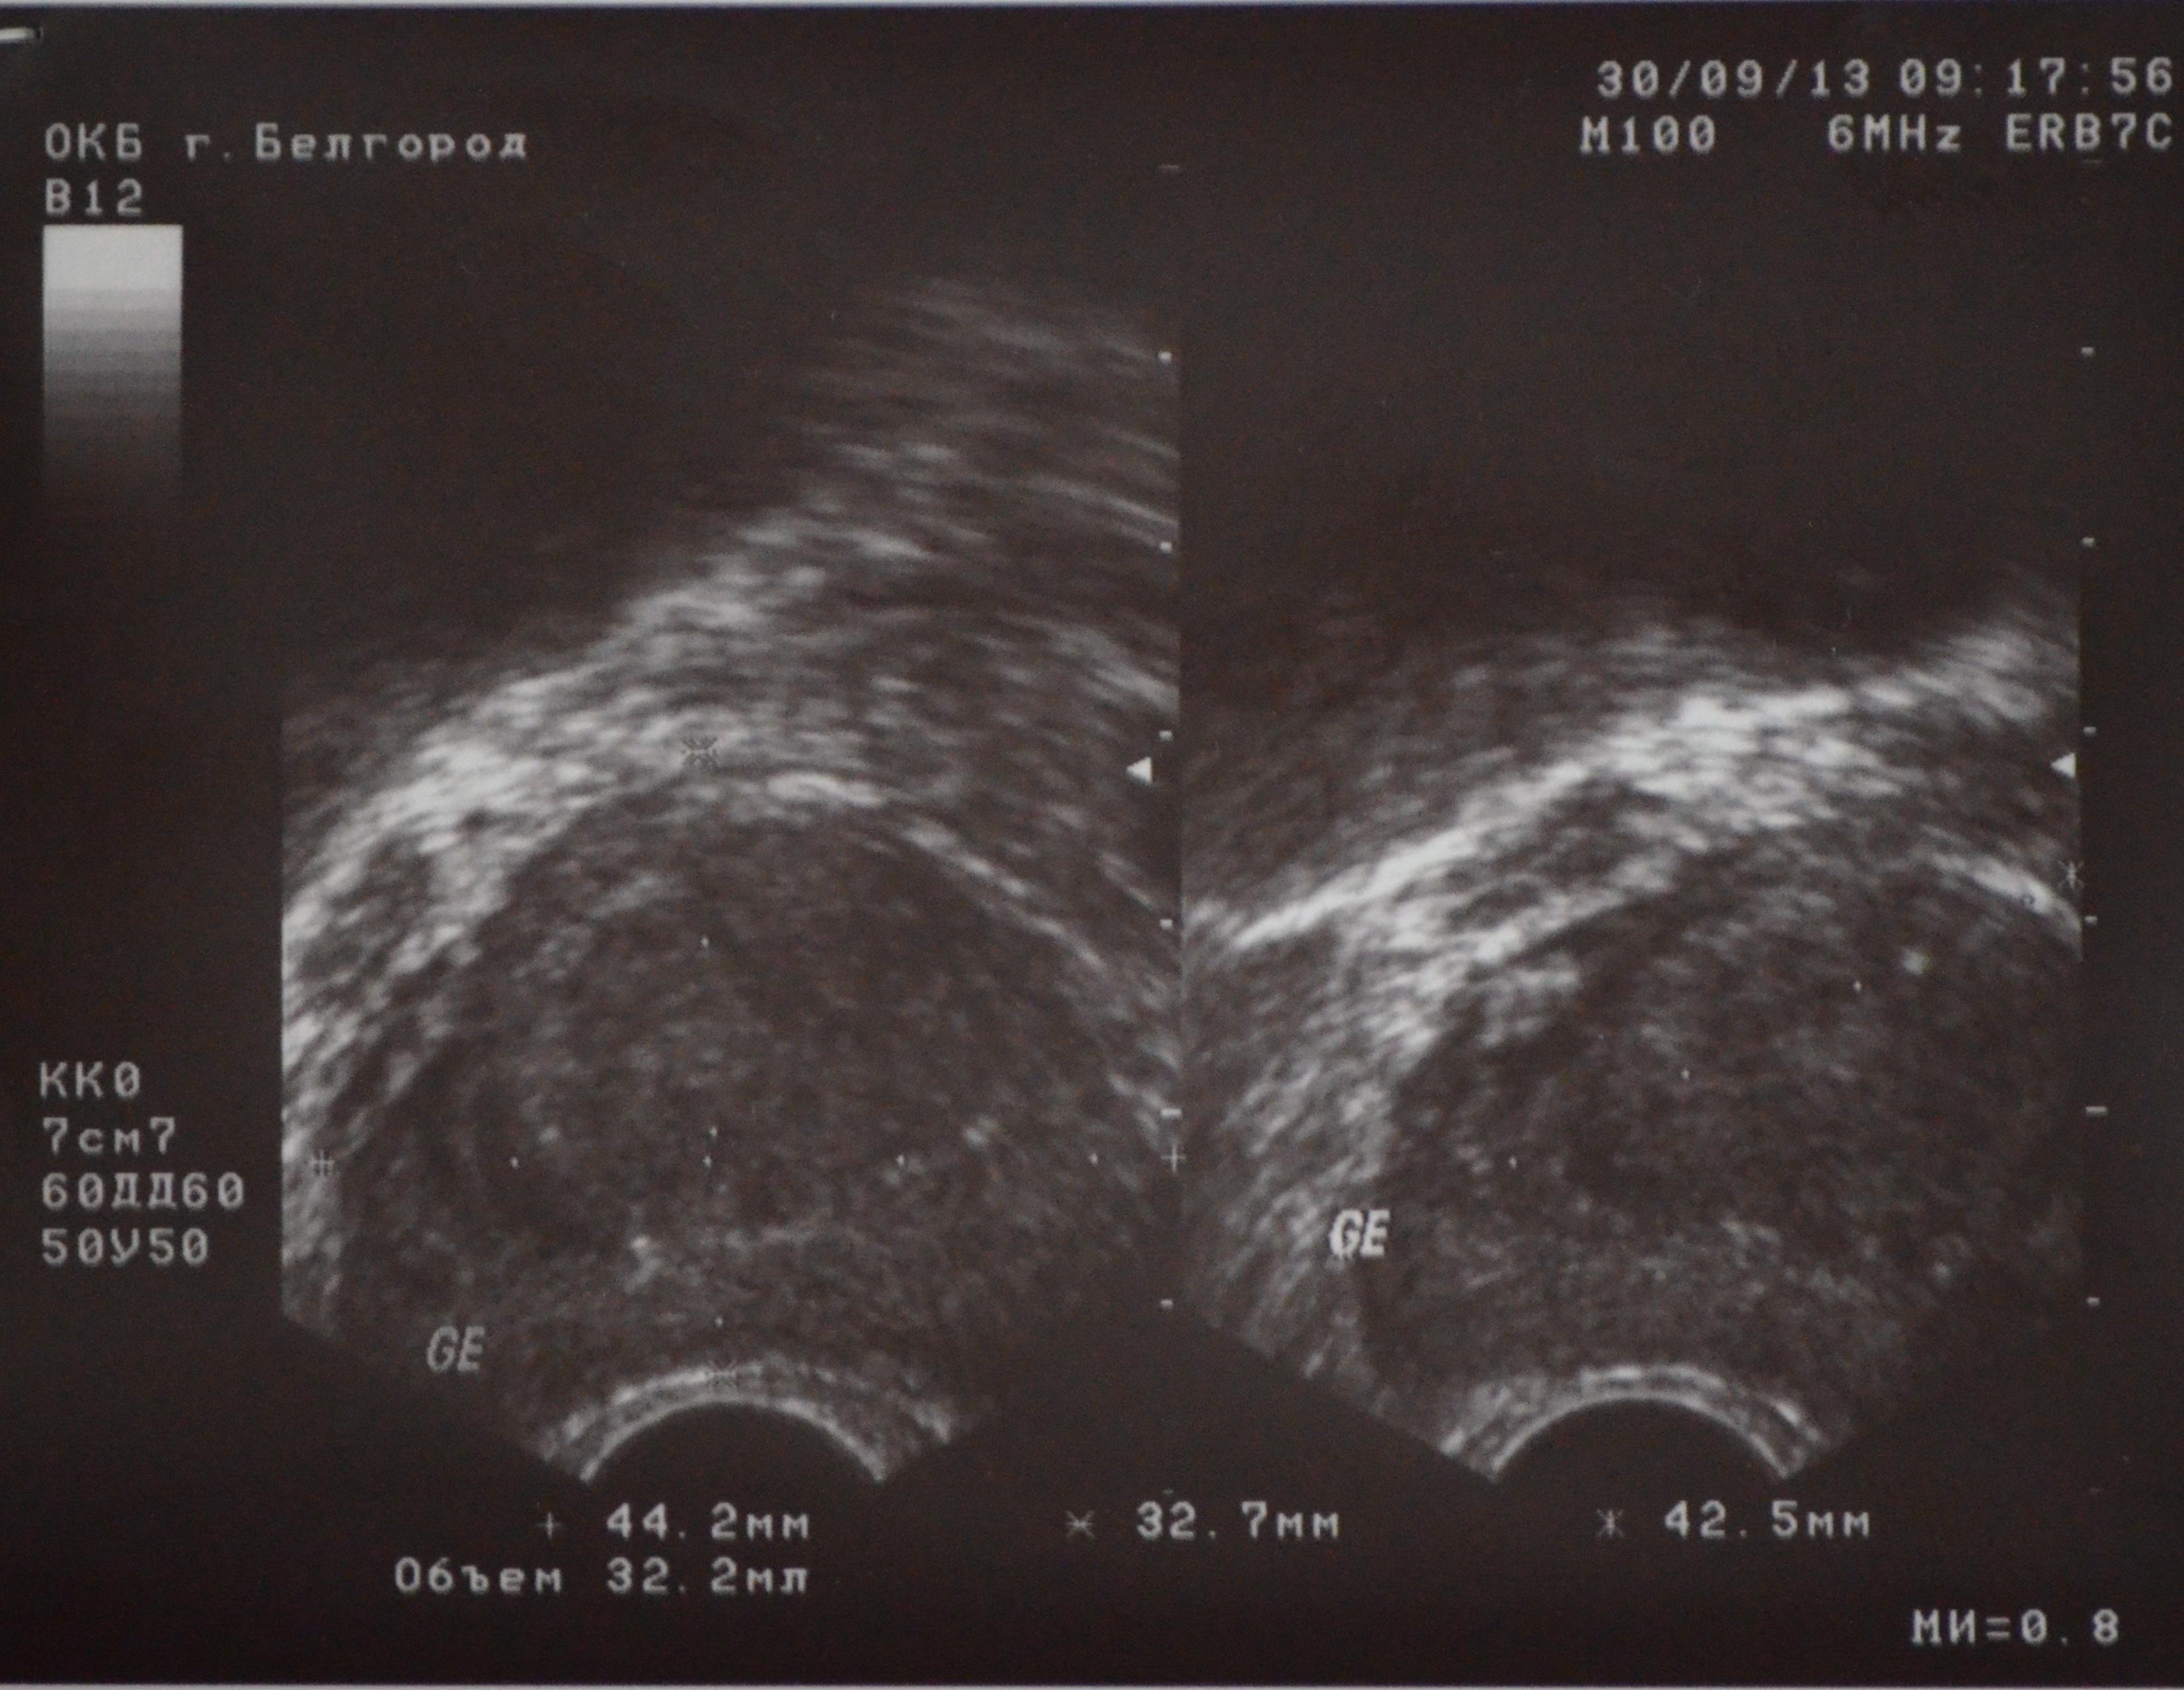

Предстательная железа – 44,2*32,7*42,5мм,(V – 32,2см3)

Контур – неровный

Эхогенность – средняя

Капсула – сохранена

Структура – неоднородная

Кальцинаты – единичные мелкие вдоль хирургической капсулы

Очаговые изменения: в периуретральных зонах образования общим размером 32*24мм

И почему размеры столь разбросаны, относительно узи? Может я не так понимаю 44,2-это толщина, 32,7-это ширина, а 42,5-это высота?

Прилагаю фото результатов.